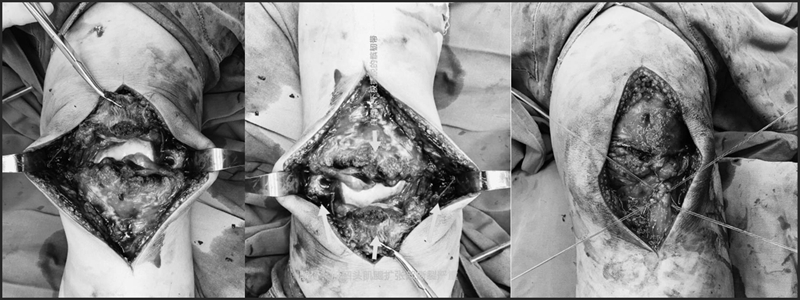

2.双套固定法

第一步“双锚钉双滑轮技术”固定:

a.在彻底清理骨折端后,在近端骨折块的两下角,斜向中线往上45度角打入两枚3.5m锚钉(注意锚钉位置尽量要靠近两侧皮质,尾部应埋入骨质)。

b.分别取两枚锚钉的同色缝线一端(绿线),用缝针或者硬膜外导针将两根缝线分别从两侧穿过髌韧带下方在髌韧带中间同一点穿出(7点)。

c.取红线重复一遍第二步操作(5点)。

d.穿髌韧带的两根同色缝线(分别来自于两个锚钉)相互打结。

蓝色线在7点,红色线在5点分别打结,每个结打6个,以保证不会滑开

e.同时拉两根同色缝线的另外一头,两个颜色缝线交替收紧,以两个锚钉尾孔为滑轮,髌韧带内缝线(线)将髌骨下极骨折块和软组织复位至原处。此手术技术可以保证在髌骨-髌韧带交界处有8根线贯穿。

f.继续重复b-d操作,完成第二轮髌骨-髌韧带缝合,蓝红线分别在第一轮出针点7点与5点的旁边5mm处,即:6点处与4点处穿出打结。

通过第1、2轮b-d操作后,髌骨-髌韧带交界处有8根线贯穿即:7、6、5、4点分别有2根线打结,一共有8根线贯穿缝合。

第三步:0号Vicryi可吸收线修复髌骨两侧的髌支持带,2-0 Vicryis缝合髌前腱膜及髌韧带断端。

术中